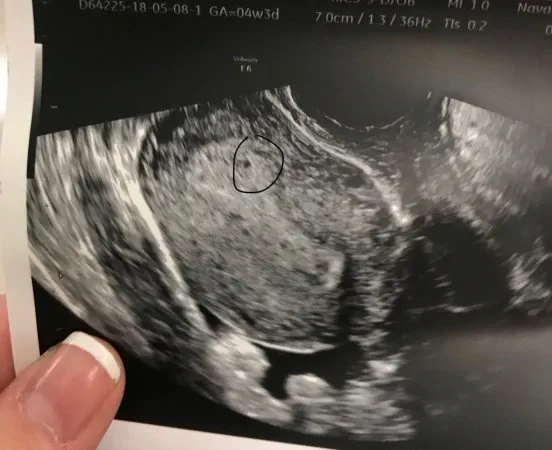

O estabelecimento provavelmente ocorreu alguns dias atrás. As coisas levam tempo para se desenvolver. É por isso que os ultrassom geralmente não são feitos antes de 8 semanas - não há nada a fazer.

É absurdamente cedo para o ultrassom. Tudo o que você espera ver é um forro espessado. Veja todas as respostas (1) - Pôster original Daxy disse: Sim, isso é normal.

O estabelecimento provavelmente ocorreu um FE inteiro ... O meu não parece muito pequeno por 4 semanas 3 dias, certo? Veja todas as respostas (1) - Pôster original Potvskettle disse: É absurdamente cedo para o ultrassom. Tudo o que você espera ver é ... Eu nunca terei o início de uma varredura novamente ... teme que nada tenha perdido um bebê. Veja todas as respostas (1)

Babyjanuary2019 disse: O meu não parece muito pequeno por 4 semanas 3 dias, certo? Parece muito bom. - Eu tinha feito uma a 4 semanas e 5 dias e não vi nada e meu dr disse que pode ser ectópico Veja todas as respostas (1)

- Eu tive um ultrassom em 4,5 semanas e eles pensaram que haviam visto algo como uma pequena bolsa, mas não tenho certeza. Fiz meus níveis de HCG repetir e voltar em alguns dias para um novo ultrassom. Eu ainda tenho esperança? Talvez muito cedo? Veja todas as respostas (1)